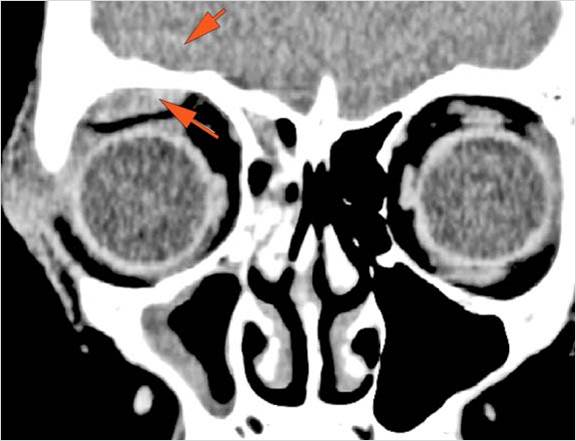

There is evidence of a subperiosteal hematoma along the medial wall, roof or floor of the orbit. [Yes/No]

The orbital apex and the superior and inferior orbital fissures are abnormal. [Yes/No]

The extraocular muscles are swollen. [Yes/No]

Proptosis is present. [Yes/No]